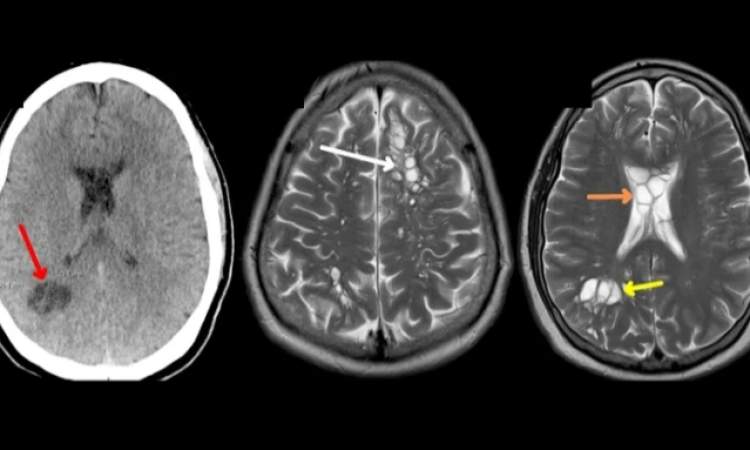

وجاء في التقرير، أنه كان يعاني من أعراض مؤلمة جدًا أسبوعيًا تقريبًا، ولم تستجب لأدوية الصداع النصفي. طلب طبيبه إجراء فحص بالأشعة المقطعية أظهر وجود أكياس متعددة مليئة بالسوائل، في جميع أنحاء دماغه. بداية اشتبه الأطباء بأن يكون مصابًا بحالة عصبية نادرة تسمى الأكياس الدبقية العصبية الخلقية، فأدخله الأطباء إلى مستشفى أورلاندو لاستشارة قسم جراحة الأعصاب.

وأظهرت المزيد من الاختبارات والتصوير في المستشفى أنٌّ الأكياس ليست إلا يرقات دودة شريطية طفيلية استقرّت في دماغه وتسبّبت بعدوى تسمى داء الكيسات المذنبة العصبي، بحسب ما جاء في التقرير.